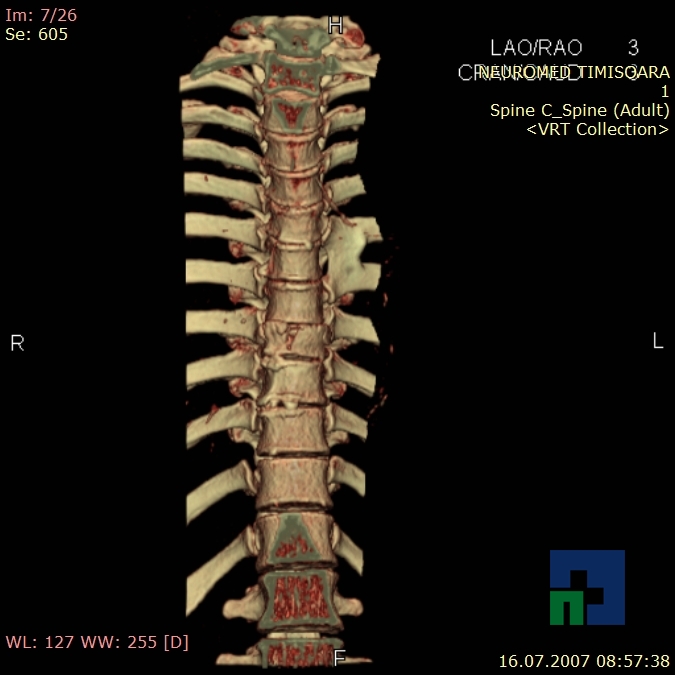

- Diagnosticul fracturilor:

- Unice

- Multiple

- Cu înfundare

- Complexe cranio-sinusale

- Complexe cranio-etmoidale

- Complexe cranio-orbitare

- Complexe cranio-faciale